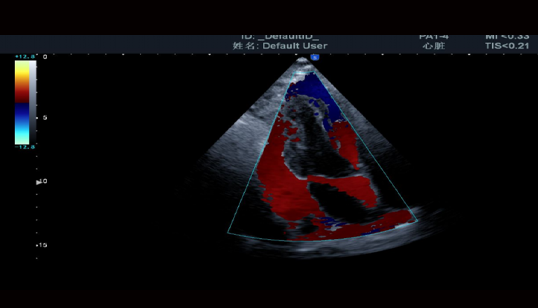

心脏成像

Heart imaging: 心脏成像

高清心脏M型成像

• 对于外形或位置异常的心脏,都能保持M型线与解剖结构垂直。三线M型在同一个心动周期内准确获得心脏组织数据。

TDI组织多普勒成像

• 用于评估心肌活动的方向和时间,显示血管壁运动和心脏组织运动速度

SRI应变率成像

• 通过对图像进行彩色编码,可用于评价心室整体和局部功能,大大增强了心脏检测的临床应用。